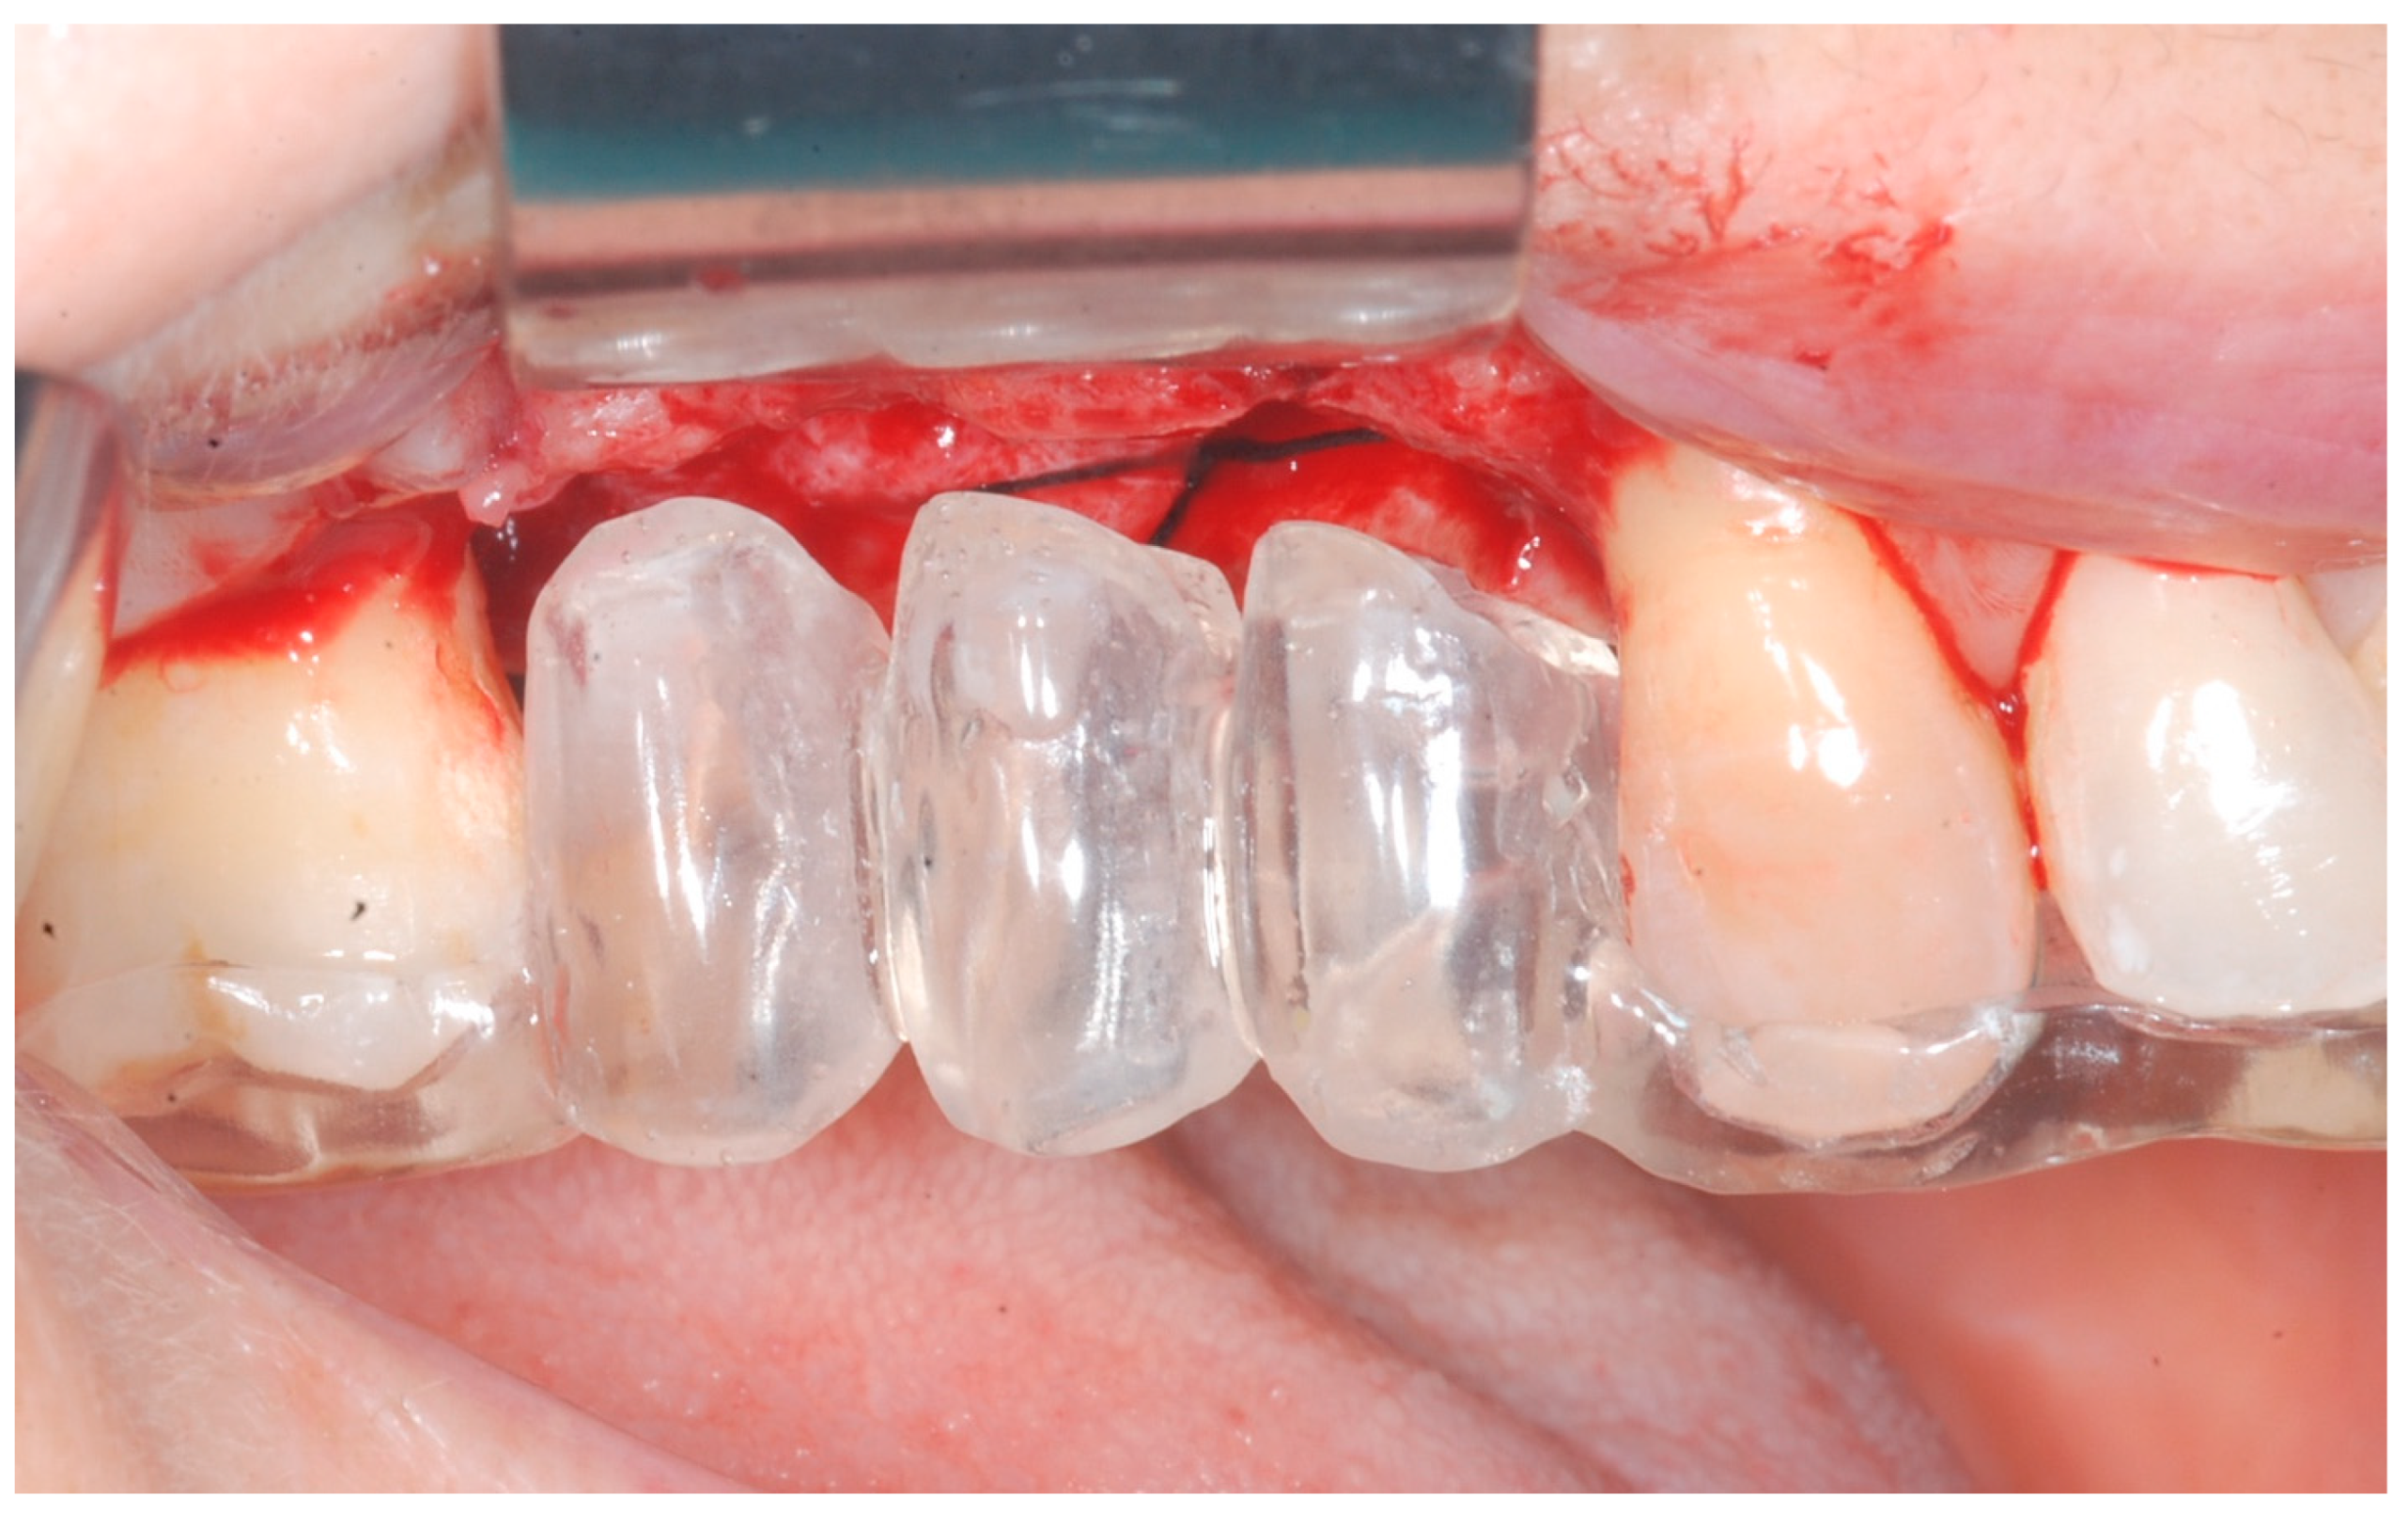

Releasing incisions were made through the periosteum at the base of the flap in order to allow tension-free adaptation of the wound margins. Horizontal mattress sutures as well as single interrupted sutures (CV-5 and CV-7, Gore-Tex; W.L. Gore & Associates, Flagstaff, AZ, USA) were placed to achieve healing by primary intention (Figure 7 and Figure 8).

Healing abutments were screwed to the implants and the flaps were sutured. Additional peri-implant plastic surgery procedures (connective tissue grafts or free gingival grafts) were performed when needed in order to have at least 2 mm of attached keratinized mucosa. The prosthetic phases began upon healing of the soft tissues, and definitive screw-retained prostheses were finally delivered (Figure 11, Figure 12 and Figure 13).

Figure 7. Tension-free sutures.

Figure 11. Delivery of definitive prosthesis.